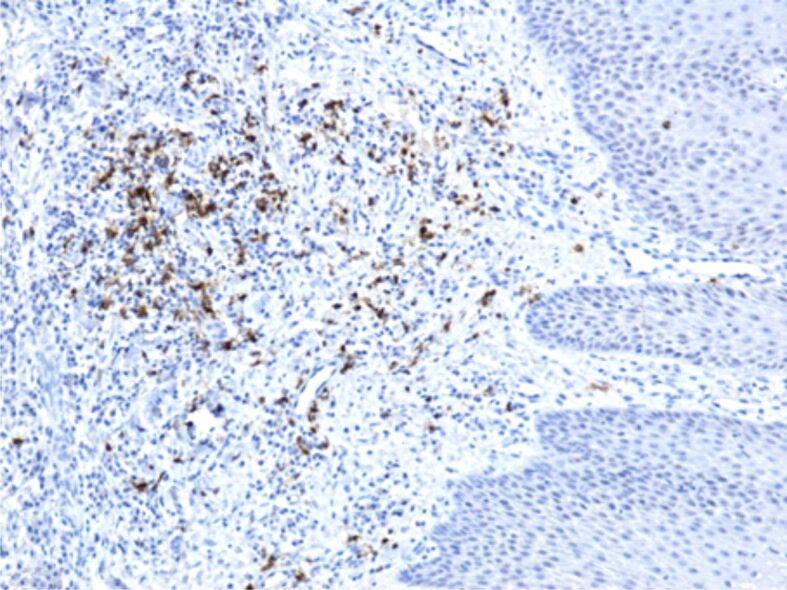

Periodontal disease is a chronic inflammatory, multifactorial condition, that, in the absence of an early and adequate treatment, may lead to a progressive damaging of the alveolar tissues that support the teeth (periodontal ligament, cement and alveolar bone) followed by teeth mobility and, subsequently, their loss. Periodontal disease is one of the most common inflammatory disease affecting adult individuals all over the world, being considered a real worldwide pandemic. This disease may influence the progression of certain systemic diseases: diabetes mellitus, cardiovascular diseases, ischemic cardiomyopathy, myocardial infarction, stroke, neurodegenerative diseases, chronic kidney diseases, cancer, etc. The association between smoking and periodontal disease was described in numerous clinical and epidemiological studies, suggesting that products derived from tobacco burning may change the clinical aspects and the disease progression. The present study analyzed microscopically and immunohistochemically 58 periodontal fragments, from 50 patients, chronic smokers, clinically diagnosed with severe periodontitis. There were highlighted major changes in the gingival epithelium (epithelium thickening, acanthosis, intraepithelial edema, infiltrates of neutrophils or lymphocytes, epithelial necrosis), in the periodontal conjunctive tissue (more or less intense inflammatory infiltrates, microhemorrhages, vascular congestion, intense immunohistochemical expression for some matrix metalloproteinases). The periodontal changes may be the expression of both toxic factors present in tobacco smoke and due to the changes caused by tobacco in the microbial flora of the oral cavity.

牙周病是一种慢性炎症性、多因素疾病,如果不进行早期和充分的治疗,可能会导致支持牙齿的牙槽组织(牙周韧带、牙骨质和牙槽骨)进行性破坏,随后牙齿松动,最终导致牙齿脱落。牙周病是全世界成年人最常见的炎症性疾病之一,被认为是一种真正的全球性流行疾病。这种疾病可能会影响某些系统性疾病的进展:糖尿病、心血管疾病、缺血性心肌病、心肌梗死、中风、神经退行性疾病、慢性肾病、癌症等。大量的临床和流行病学研究描述了吸烟与牙周病之间的关系,表明烟草燃烧产生的产物可能会改变疾病的临床特征和进展。本研究通过显微镜和免疫组织化学分析了 50 名慢性吸烟者的 58 个牙周组织切片,这些患者均被临床诊断为严重牙周炎。结果显示,牙龈上皮(上皮增厚、棘皮病、上皮内水肿、中性粒细胞或淋巴细胞浸润、上皮坏死)和牙周膜结缔组织(或多或少强烈的炎症浸润、微出血、血管充血、某些基质金属蛋白酶的强烈免疫组织化学表达)出现了重大变化。牙周组织的变化可能是烟草烟雾中存在的有毒因素以及烟草引起的口腔微生物菌群变化的共同作用结果。